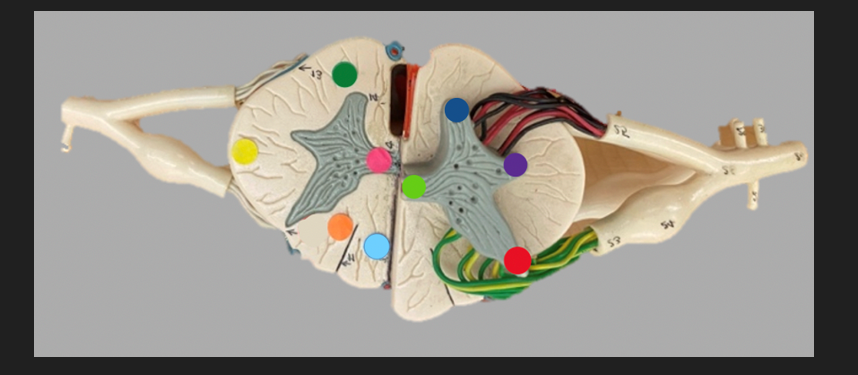

green dot

spinal nerve

orange dot

ventral root

pink dot

dorsal root

blue dot

dorsal root ganglion

red dot

dorsal ramus

yellow dot

ventral ramus

purple dot

anterior median fissure

red dot

posterior (dorsal) horn

purple dot

lateral horn

dark blue dot

anterior (ventral) horn

orange dot

dorsal column

yellow dot

lateral column

dark green

anterior column

line green and pink doit

gray commissure

light blue dot

posterior median sulcus